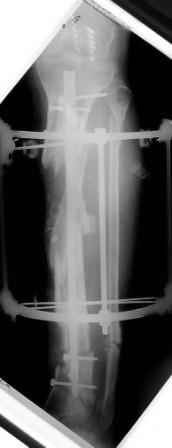

- Была выполнена репозиция в аппарате (рис1)

2) После репозиции более очевидна стала проблема дефекта кости в верхней трети голени, два фрагмента свободно лежат. Остановились на варианте перехода на интрамедуллярный синтез стержнем с покрытием костный цемент+ванкомимцин и замещении дефекта с помощью транспорта фрагмента (рис 2)